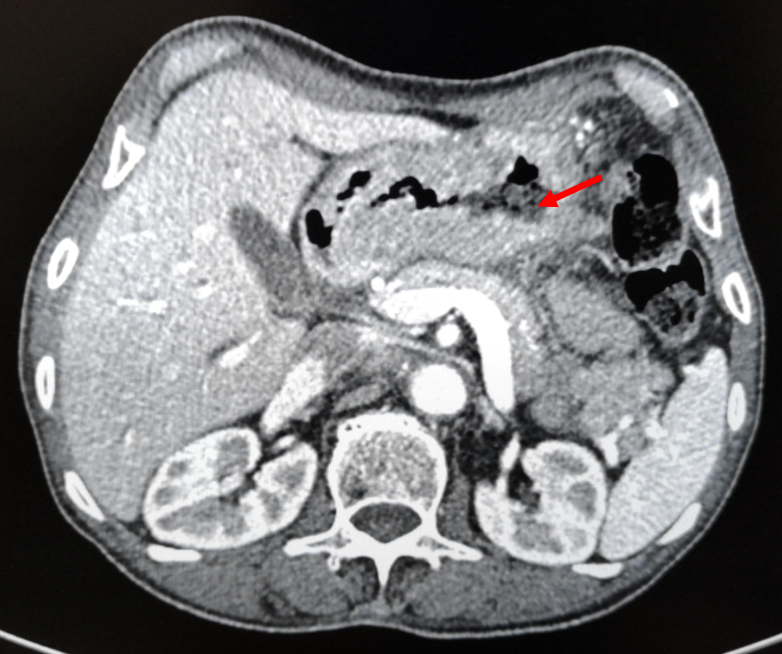

图1-2 2018-4-4 箭头为胃部肿瘤,胃壁增厚明显

腹盆腔强化CT(2018-4-4):1、胃体及胃窦胃壁增厚,考虑胃癌;2、胃周、胃左动脉区及腹膜后多发肿大淋巴结,考虑转移;3、肝内胆管结石,肝内胆管轻度扩张;4、左肾囊肿,左肾上腺增厚,考虑增生;5、前列腺增生伴钙化;6、盆腔少量积液;7、两下肺实变索条,左侧胸腔少量积液。